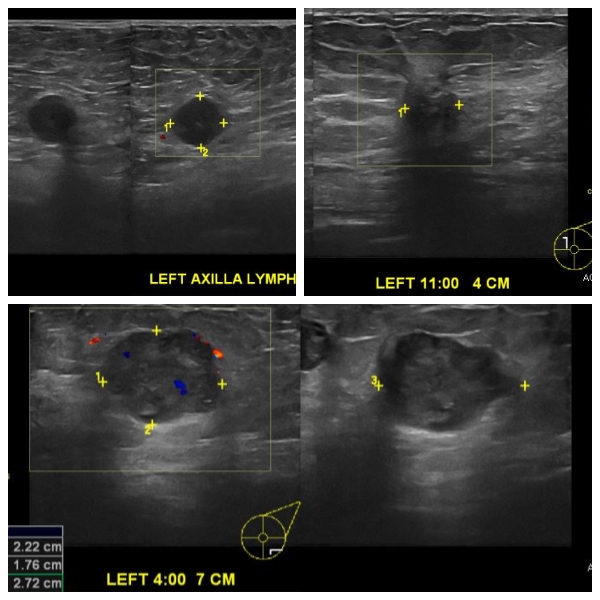

건강 검진상 이상 소견으로 내원하신 80대 여성 분으로 본원에서 초음파 시행 후 좌측

4 방향에서 7m 떨어진 거리의 혹, 11 방향에서 4cm 떨어진 혹 중앙핵생검 시행 하여

침윤성 소엽암 진단 되었으며, 좌측 겨드랑이 림프절 비대 세침검사 시행하여 전이암

으로 진단 되었습니다.